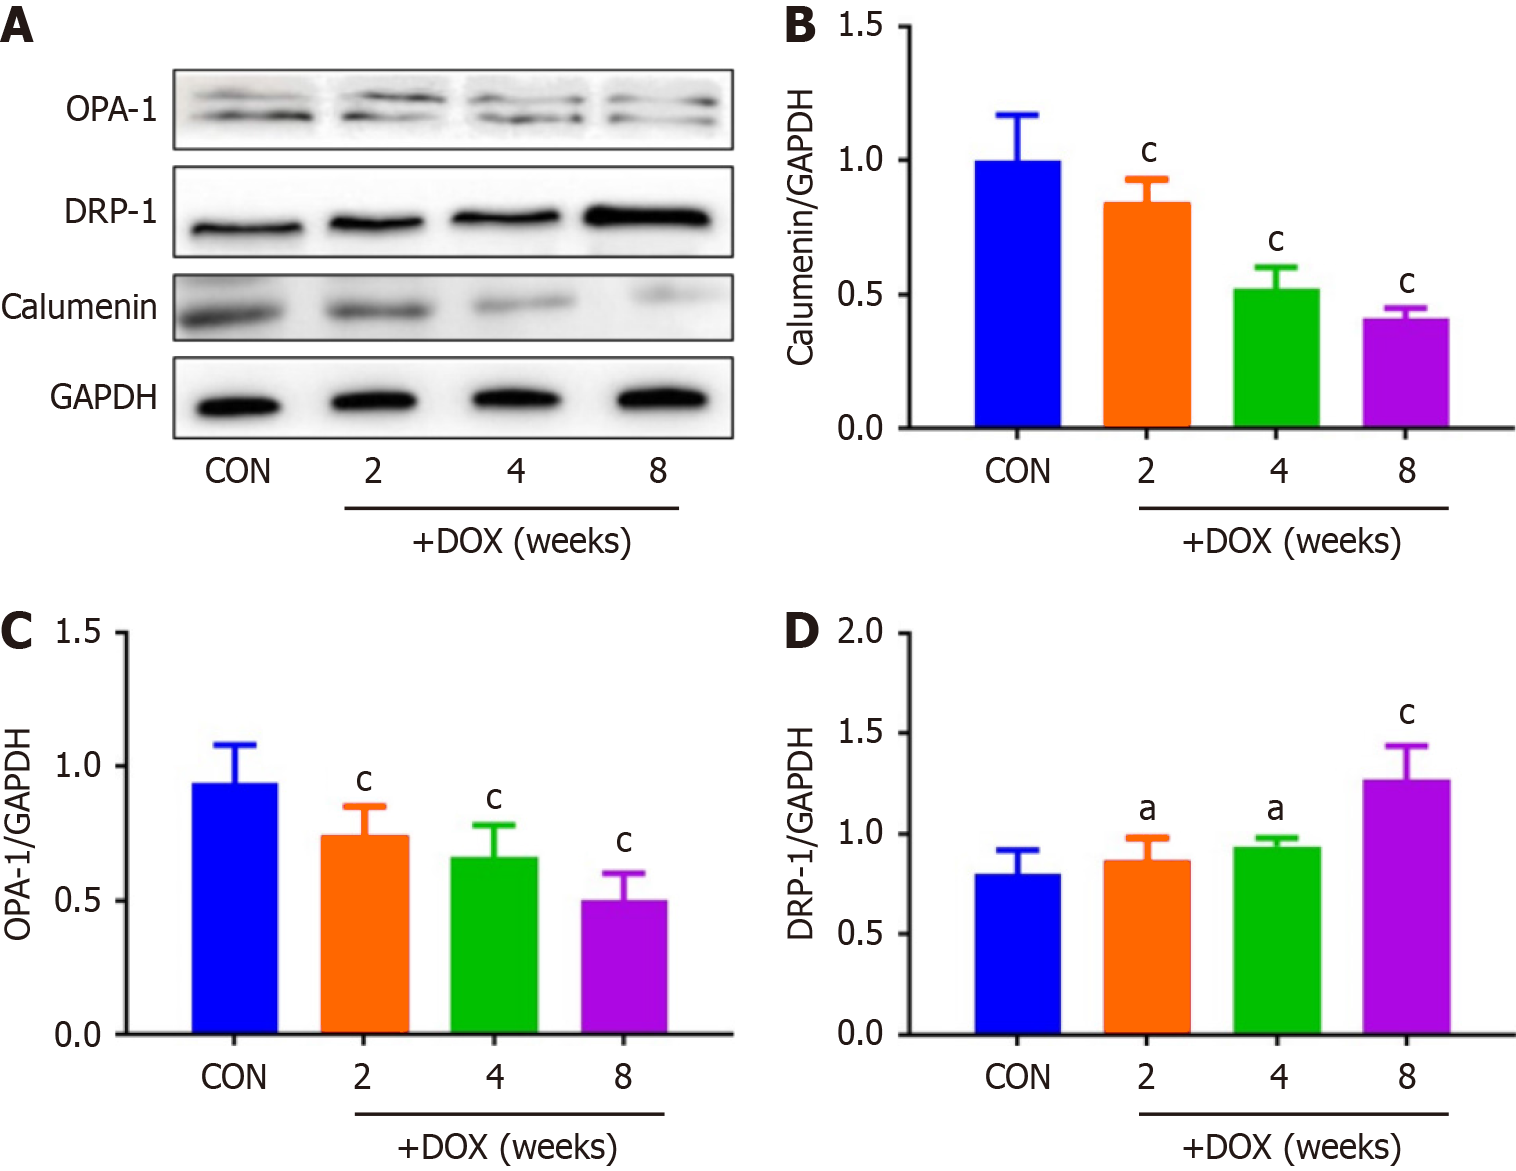

DOX reduced the expression of CALU in vivo in the DOX group, compared with the CON group (Figure 5). OPA-1 was decreased and DRP-1 was increased in the DOX group, compared with the CON group (Figure 6). To confirm the role of mitochondrial-induced apoptosis, we analyzed the expression of CytC, CHOP, Bax and Bcl-2. DOX increased expression of CytC, CHOP and Bax and reduced expression of Bcl-2 in the DOX group (Figure 7).

It has been reported[22] that CALU plays an important role in the occurrence and development of acute myocardial ischemia, arrhythmia and other diseases. Our results also showed that expression of CALU was significantly decreased in the DOX group compared with the CON group. This indicated that expression of CALU was decreased by DOX. We found that DOX decreased rat body weight, and increased the heart weight–body weight ratio. DOX reduced expression of CALU due to Ca2+ overload, and increased apoptosis of myocardial cells. In vivo experiments showed that DOX reduced expression of CALU, OPA-1 and Bcl-2, and increased expression of DRP-1, CytC, CHOP and Bax in rats.

We found that DOX decreased expression of CALU and mitochondrial fusion proteins, increased expression of mitochondrial split proteins, and increased the cytoplasmic calcium concentration of cardiomyocytes. CALU is a calcium-binding protein found in the lumen of the endoplasmic reticulum. If the expression of CALU is reduced in cardiomyo